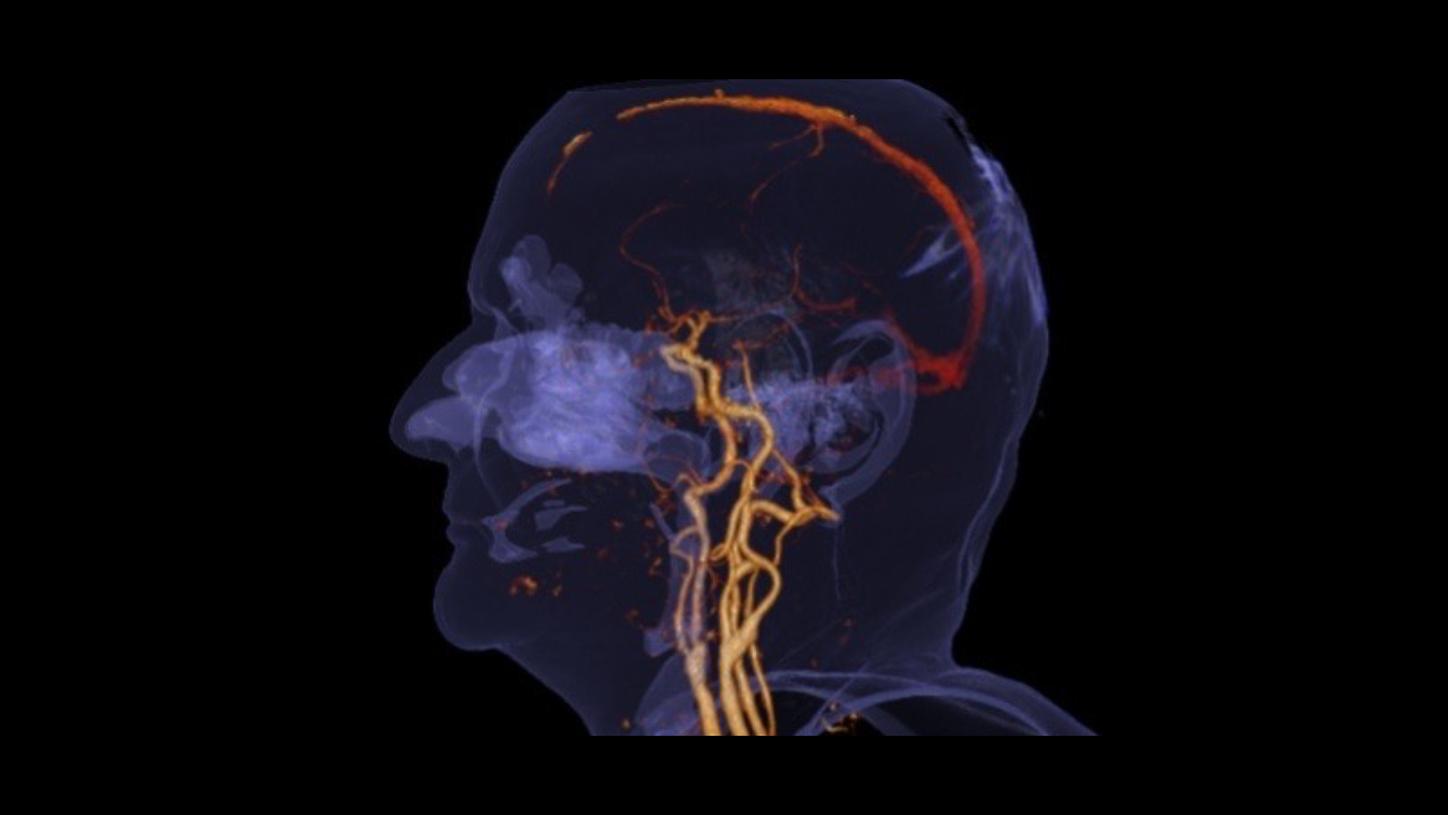

Cinematic VRT

Clearly visualize clots and get photorealistic and easy-to-understand material for education, publication, and communication

Cinematic VRT

Clearly visualize clots and get photorealistic and easy-to-understand material for education, publication, and communication